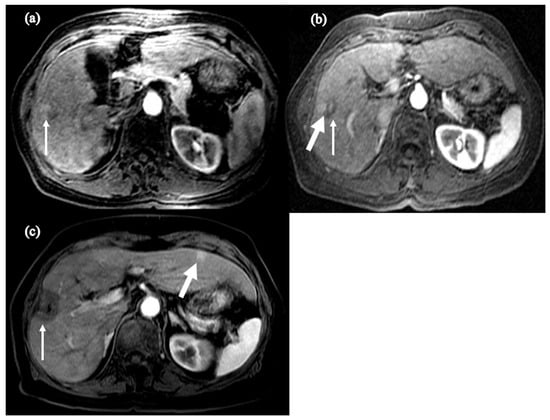

- Shinn, B.J.; Martin, A.; Coben, R.M.; Conn, M.I.; Prieto, J.; Kroop, H.; DiMarino, A.J.; Hann, H.W. Persistent risk for new, subsequent new and recurrent hepatocellular carcinoma despite successful anti-hepatitis B virus therapy and tumor ablation: The need for hepatitis B virus cure. World J. Hepatol. 2019, 11, 65–73. [Google Scholar] [CrossRef] [PubMed]

- Boortalary, T.; Shinn, B.; Coben, R.M.; Conn, M.I.; Prieto, J.; Kroop, H.; Dimarino, A.; Hann, H. Are We Close to Achieving a HBV Cure? Risk for Hepatocellular Carcinoma Persists Despite Long-term HBV Suppression: An Update on Our Experience. Arch. Gastroenterol. Res. 2020, 1, 105–110. [Google Scholar]